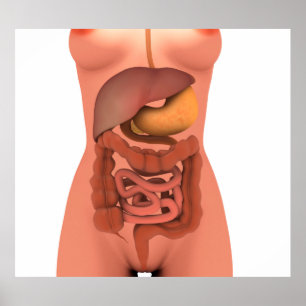

Carta do poster da anatomia do órgão interno do

Preço56,50 €

Impressão humano da anatomia dos órgãos interno

Preço15,60 €